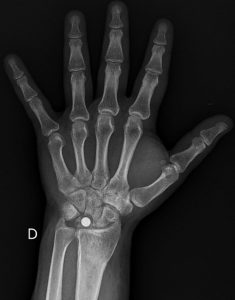

La maladie de Kienböck est une pathologie rare du poignet qui touche l’os semi-lunaire (en rouge sur la figure 1). Elle se caractérise par la nécrose du lunatum. Cette nécrose osseuse est la conséquence d’un manque de vascularisation sanguine destiné à cet os. L’os perd sa solidité et peut progressivement se fracturer. Cette maladie entraîne généralement des douleurs, des raideurs et une perte de mobilité du poignet, affectant la qualité de vie. Elle évolue vers l’arthrose du poignet.

L’imagerie joue un rôle essentiel dans le diagnostic de la maladie de Kienböck et permet de déterminer son stade. La radiographie standard reste le premier bilan à réaliser. Elle permet de voir les fractures ou la déformation du lunatum dans les formes avancées de la pathologie. Cependant, les premiers stades de la nécrose peuvent ne pas être visibles sur les radiographies classiques.